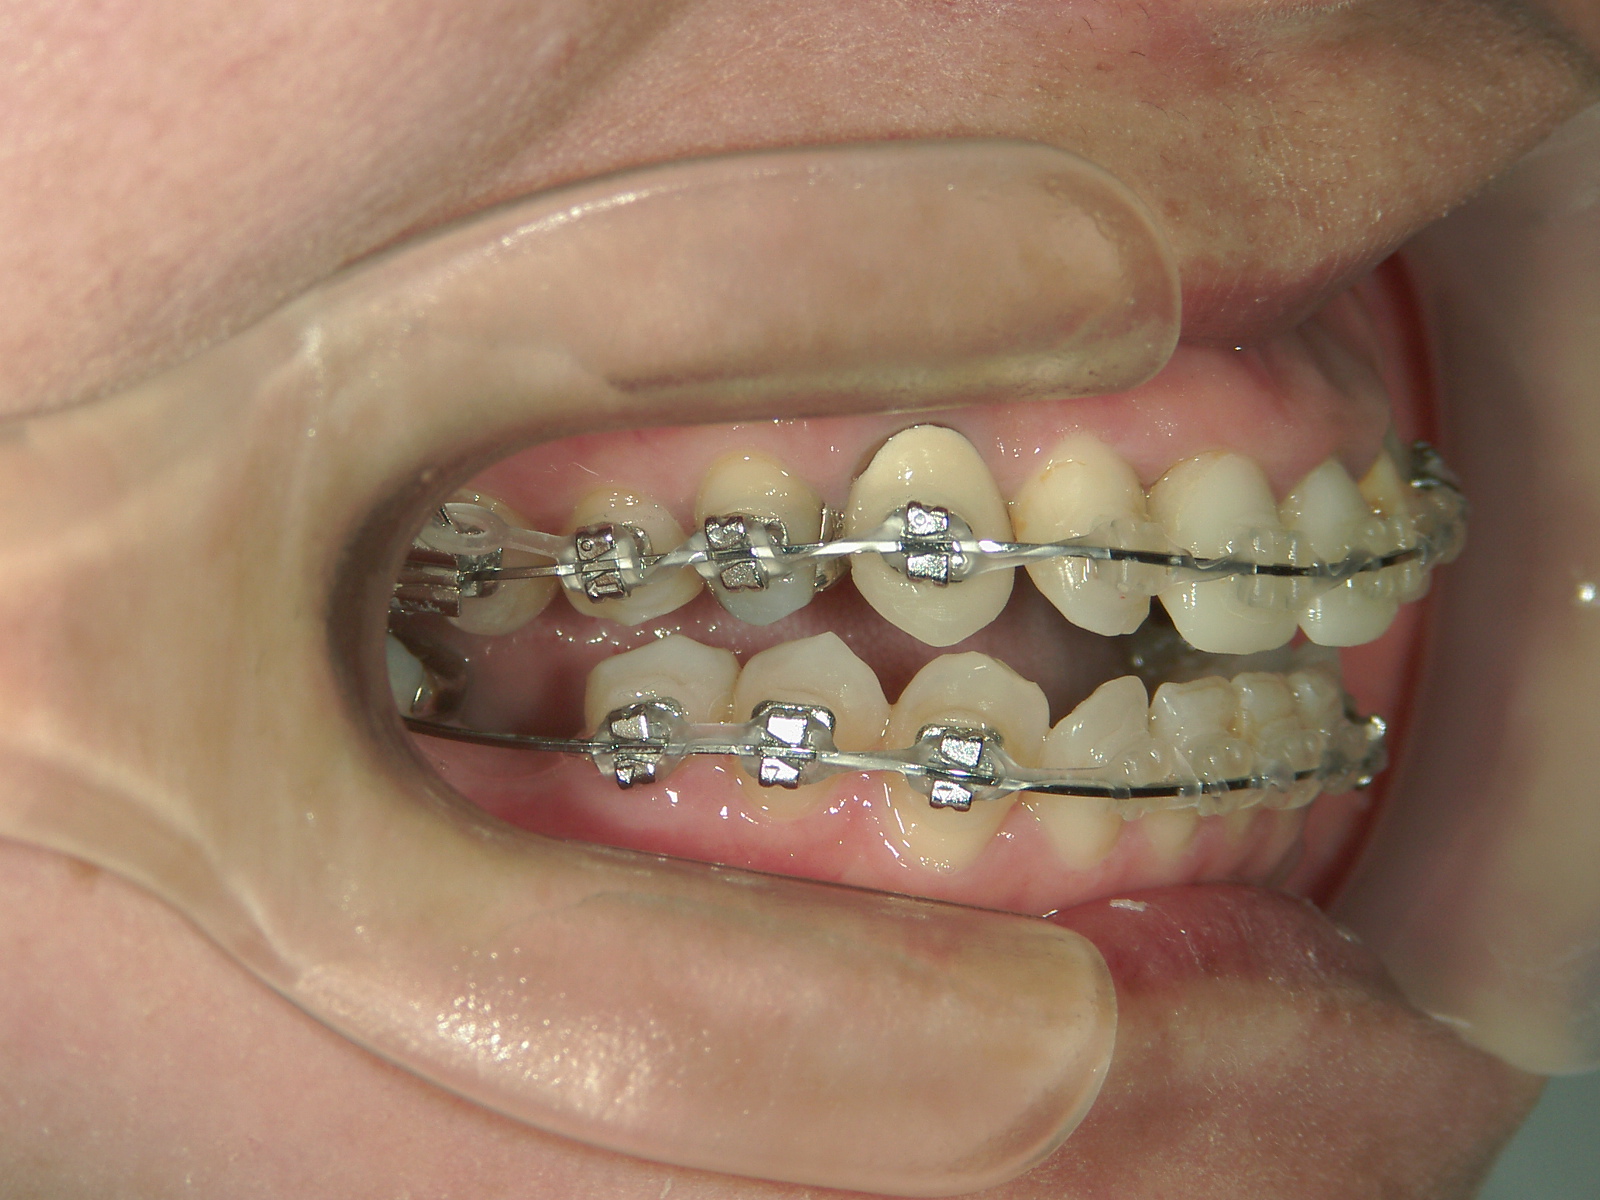

抜歯欠損症例(7)右下大臼歯 欠損・左下大臼歯 抜歯

主訴: 前歯揃えて引っ込めたい

右下 第一大臼歯 欠損。

右上 親不知1本、左下 第一大臼歯1本を抜歯。

ミニインプラント併用。

㊤前歯2本冠せ物をセラミックへ変更。